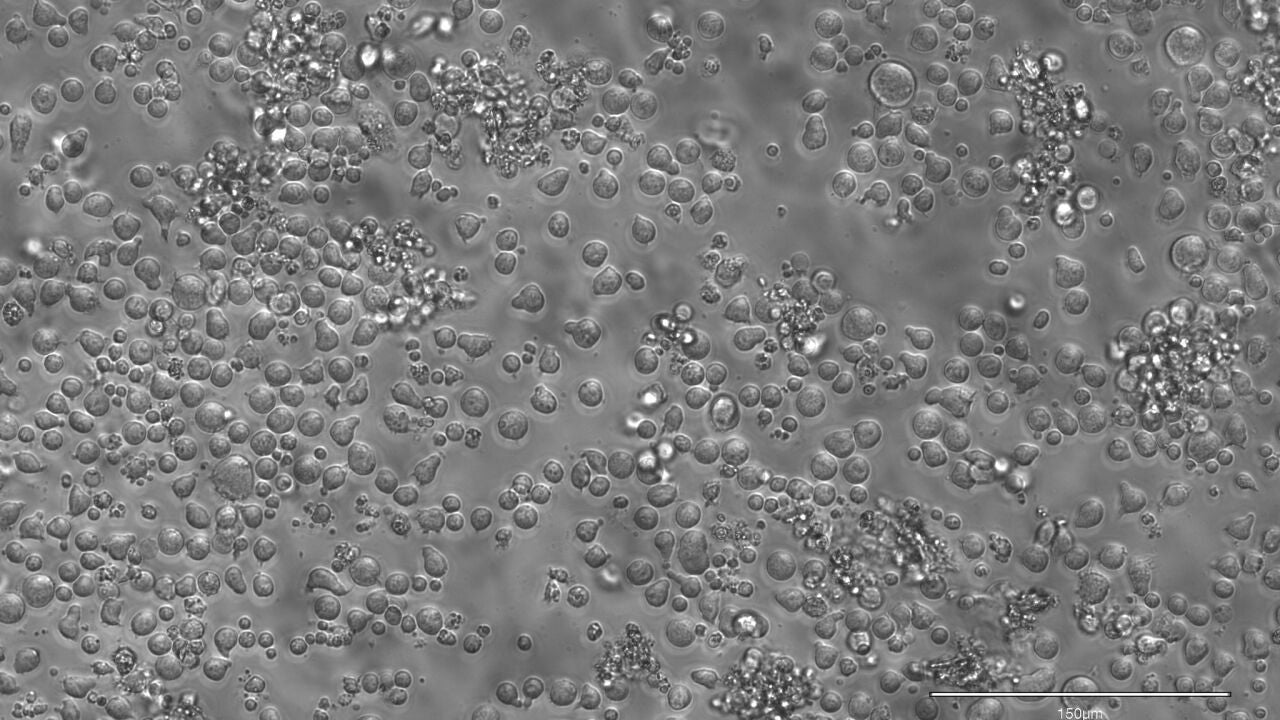

Para ello, los investigadores desarrollaron EPI-Clone, una técnica gracias a la cual es posible leer estos códigos de barras de metilación en cada una de las células y de esta manera pudieron generar mapas que revelan información acerca de qué células madre se expanden y, por lo tanto, contribuyen a la sangre y cuáles se extinguen a lo largo del tiempo.

Gracias a ello, los investigadores pudieron observar que en la sangre de las personas jóvenes hay una gran cantidad de células madres diferentes, las cuales producen un conjunto diverso y variado de células, mientras que a edad avanzada, principalmente a partir de los 50 años, unas pocas se imponen a sus vecinas, tomando gradualmente el control de la producción de sangre. A partir de los 60 años de edad, este fenómeno es aún más evidente y pronunciado.